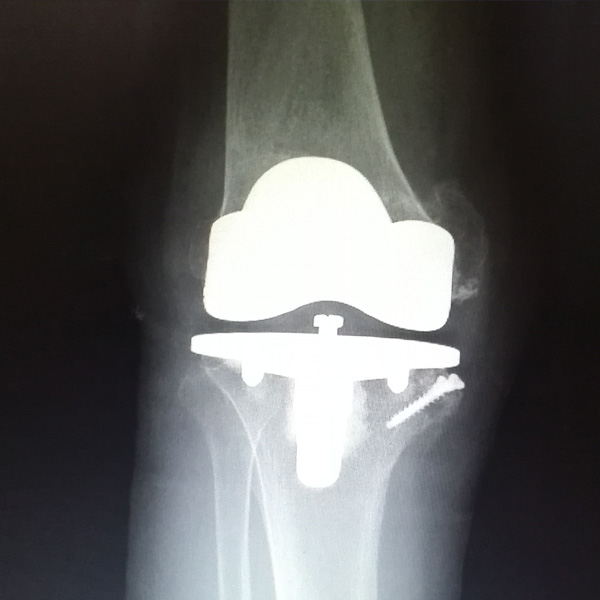

• 膝關節內翻膝關節內翻手術后手術前

膝關節內翻

患者劉某某,女66歲,左側膝關節嚴重內翻(俗稱的“羅圈腿”),疼痛到不能生活自理。經平臺推薦到哈爾濱醫科大學附屬第二醫院骨關節科就診,......